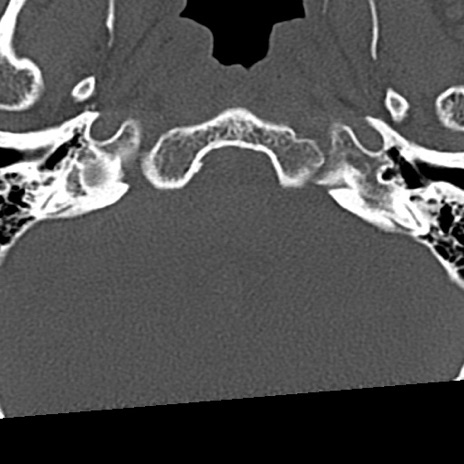

頚椎CT

冠状断像